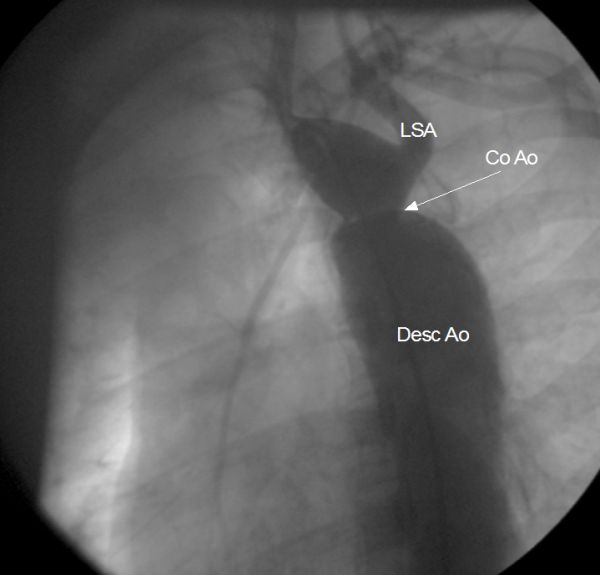

Coarctatie de aorta

<

Coarctatia aortei ar trebui corectata anterior sarcinii.

Este rara in timpul sarcinii (9% din defectele

congenitale). Managementul hipertensiunii arteriale

este dificil la pacientele gravide neoperate.

Dezvoltarea fetala este de obicei normala si, in

contrast cu hipertensiunea arteriala esnetiala,

preeclampsia nu apare, dar un tratament prea agresiv al

hipertensiunii arteriale poate cauza perfuzie scazuta a

segmentelor distale. Aceasta poate cauza avort sau

moarte fetala chiar daca tensiunea arteriala in

segmentele proximale continu sa creasca la efort.

Ruptura aortica este cea mai frecventa cauza de deces

si ruptura unui anevrism din poligonul Willis a fost

raportata in cursul sarcinii. Cresterea volumului

sanguin si a debitului cardiac creste riscul de disectie

sau ruptura aortica in timpul saricinii, motiv pentru

care ar trebui instituit tratament cu beta-blocant.